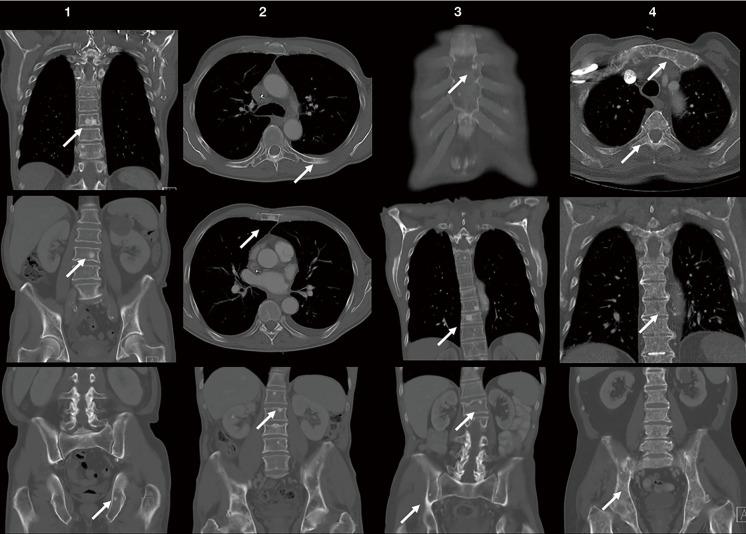

This retrospective study analyzed 118 GC patients treated at our institution from 2010 to 2020. Among them, eight patients (6.8%) developed BM, with an equal split between osteoblastic and osteolytic types. Osteoblastic BM was observed exclusively in men, with a mean age of 72.25 years. The median time from GC diagnosis to BM onset was 27.5 months. BM was primarily detected through periodic thoracoabdominal CT scans, and bone scintigraphy confirmed the osteoblastic nature of the lesions. All patients had advanced GC and were under palliative care at the time of BM diagnosis. The average survival time from BM diagnosis was 8.5 months.

BM in GC patients is rare but significantly worsens the prognosis. The findings suggest that osteoblastic BM may be more common in GC than previously reported, potentially due to improved imaging techniques and extended patient survival. This study underscores the importance of vigilant radiological monitoring in GC patients, particularly those with non-specific symptoms suggestive of BM. Enhanced collaboration between oncology and palliative care teams is essential to manage symptoms effectively and improve patient quality of life. Future research should focus on the incidence and management of BM in GC, particularly the role of targeted therapies in improving patient quality of life.